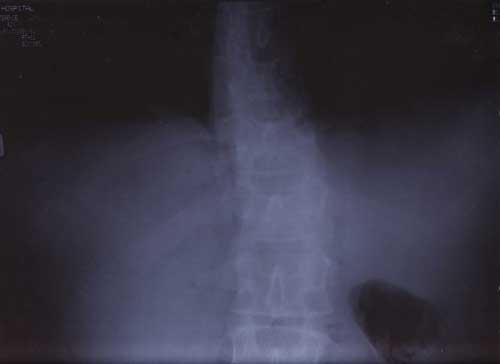

X Rays

21st January 2000